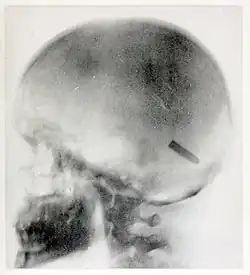

1898 berichteten amerikanische Zeitungen über die Ergebnisse ihrer Arbeit, bei der kommerziell gehandelte Lebensmittel mit Röntgenstrahlen untersucht wurden, um Verunreinigungen festzustellen. Im Dezember 1898 begann sie als Radiografin für die US-Armee zu arbeiten, die verwundete Soldaten aus dem Spanisch-Amerikanischen Krieg über San Francisco in die USA zurückschickte. Am 20. August 1899 machte sie eine ihrer berühmtesten Röntgenaufnahmen, die ein 7-mm-Mauser-Projektil im Gehirn von John Gretzer Jr. zeigt, der auf den Philippinen verwundet worden war. Berichte über den Fall wurden 1902 im International Text-Book of Surgery und weiteren Zeitungen veröffentlicht. Auch über einen weiteren Fall eines Projektils im Schädel eines von Fleischman geröntgten Soldaten wurde 1899 in Zeitungen berichtet. Ihre Arbeit während des Spanisch-Amerikanischen Krieges wurde vom Surgeon General der US Army, George Miller Sternberg, gelobt. Einige ihrer Röntgenbilder dienten dem Chirurgen William Cline Borden zur Illustration seines Buches über die medizinische Verwendung von Röntgenstrahlen im Spanisch-Amerikanischen Krieg.